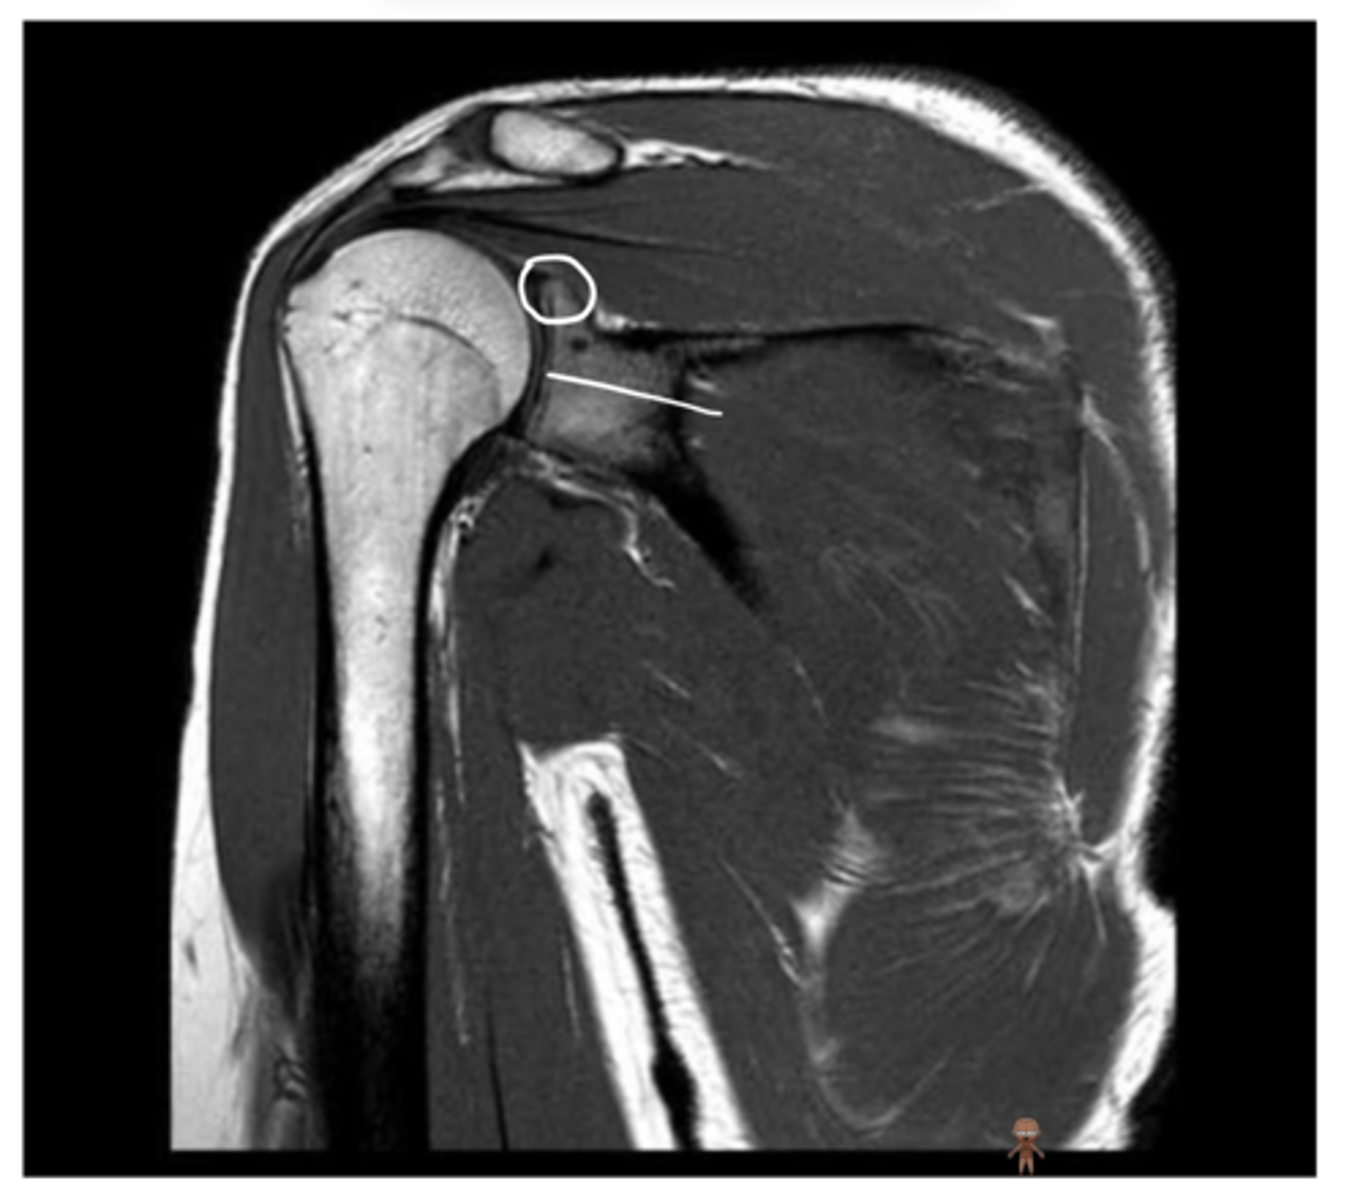

Right where the pointer is -- this is where the supraspinatus attaches to the humerus

If there was a supraspinatus tear, where would you see it? Why?

1. Lateral deltoid

2. Acromion

3. Clavicle

4. Supraspinatus footprint

5. Glenoid

Working our way around clockwise, which structures are being pointed to?